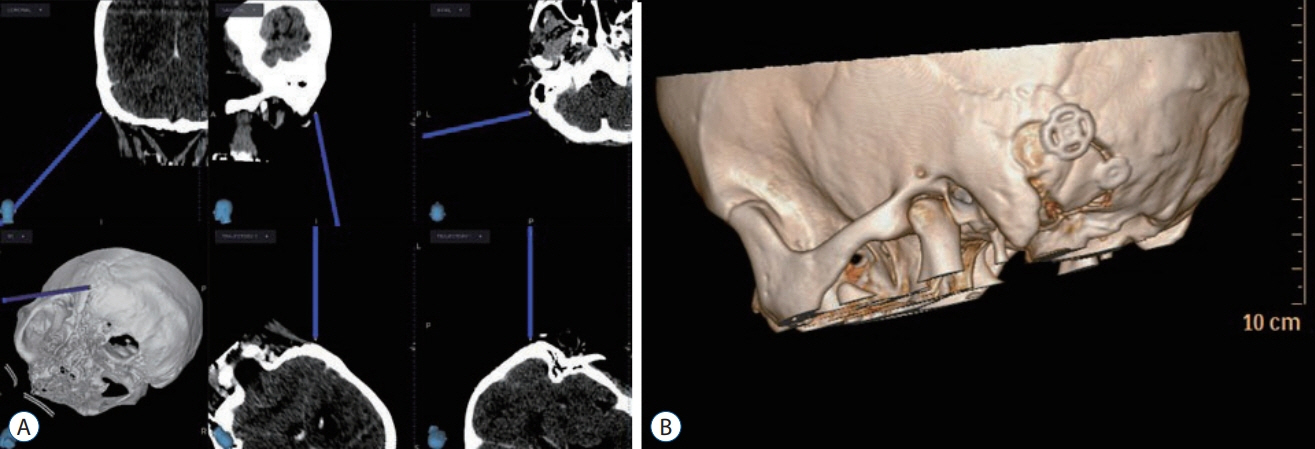

- Glossopharyngeal neuralgia (GPN) is a rare disease that must be differentiated from trigeminal neuralgia. The purpose of this article is to provide a comprehensive review of anatomy, pathophysiology, diagnostic criteria, and several options of treatment for GPN. Lessons learned through our experience of treating GPN are presented in detail, as well as cases of misdiagnosis and diagnostic pitfalls. Microvascular decompression (MVD) should be primarily considered for medically intractable GPN. Techniques employed in MVD for GPN are categorized and described. Especially, we underscore the advantages of the ‘transposition’ technique where insulating material is positioned ‘off’ the root entry zone (REZ), instead of ‘on’ it. We believe this ‘off-the-REZ’ technique can fundamentally prevent recurrence, if applicable. In addition, Gamma Knife radiosurgery can be an alternative option when a patient is ineligible for MVD, though it is categorized as a destructive procedure.